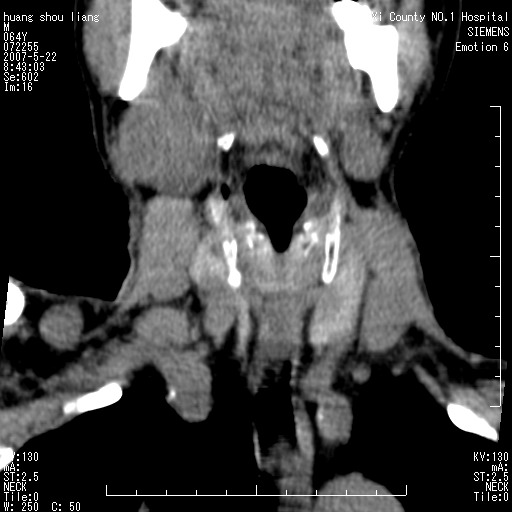

男性,64岁。颈部包块8年。最近增大。

对不起大家,可能是片子发太多有点乱,正常腮腺在下颌角的外侧,颌下腺在下颌体的中部内侧,本例在下颌角内侧偏下,和腺体一点关系都没有,从vrt和mpr上可以很明显看出来,再者肿块是好多粘连在一块的,大家在仔细看看,左侧可能也是吧,我还是考虑为肿大的淋巴结融合在一块,但性质??????

右侧腮腺下部均匀软组织密度肿块,外形不规则,与周围组织分界清晰,考虑右侧腮腺混合瘤或多形性腺瘤。

大家好,病理结果出来了,如大家所说,颌下腺混合瘤。

唉,解剖没学好吧,我诊断错了,不过还是有些不理解回去我在多看看书,谢谢大家的参与,以后我还会奉献好的病例。